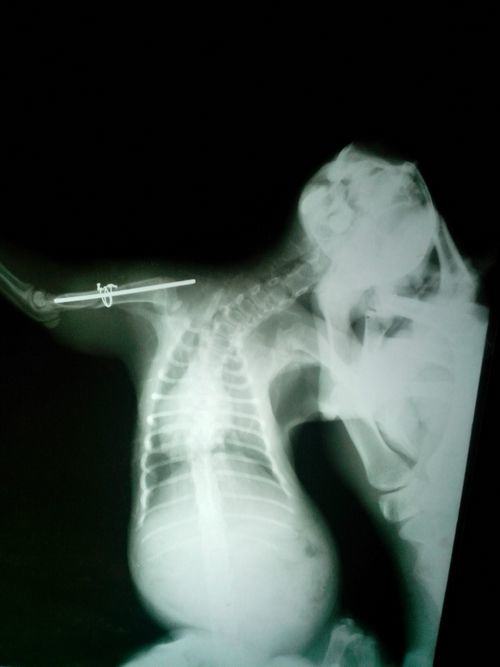

由于猫个体较小,没有合适的骨板,并且属于典型的长斜骨折,于是选用髓内针配合钢丝环扎的技术来进行固定。首先将肱骨复位,预先钻孔埋置好半环扎的钢丝和全环扎的钢丝,选择合适大小的髓内针逆向进针从从肱骨结节外侧穿出,再将整个髓内针打入骨骼中央,固定牢固后将钢丝收紧。闭合切口时,缝合臂头肌,臂肌韧带的表层肌肉。常规缝合皮下组织和肌肉。

图为术后X光图,肱骨基本恢复正常形态,但是骨折线没有对齐,后期可以通过形成骨架慢慢愈合